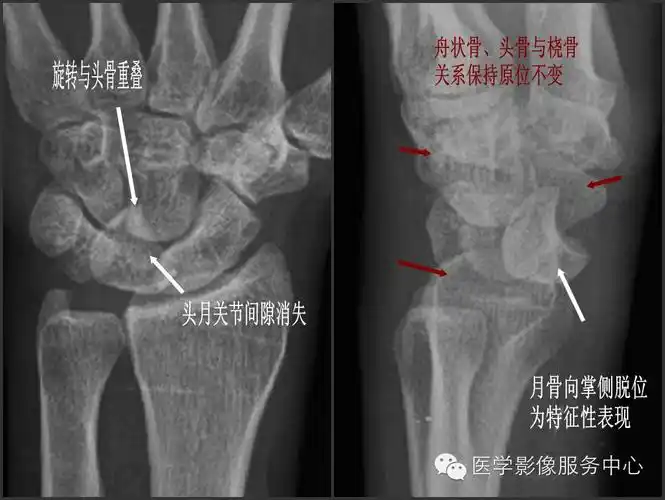

【读片】腕关节脱位 [病例帖]

脱位为特征性表现;①正位片月上骨旋转与头骨重叠,头月关节,桡月关节

腕骨脱位丨分类及表现